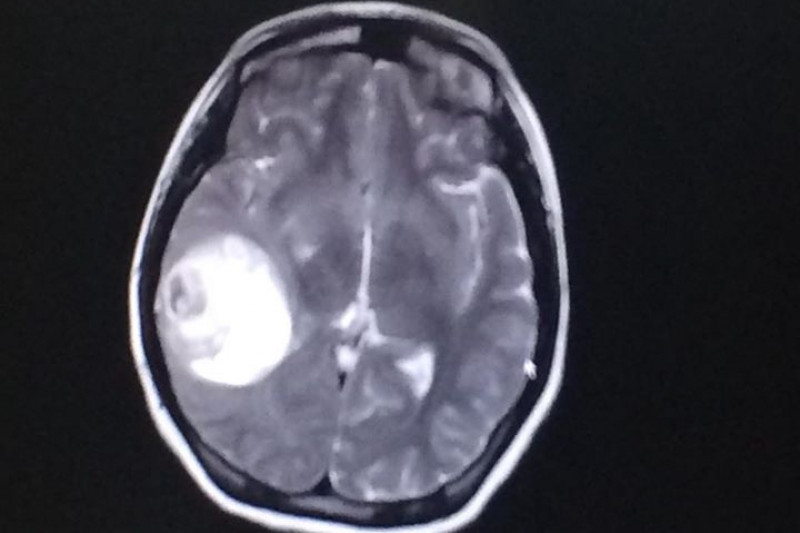

I have suffered from chronic migraines for years. This past Wednesday, I had a seizure at work where it was discovered that I had been living with a 5cm brain tumor. I had a craniotomy Friday, December 29th and was discharged from the hospital Sunday, December 31st (New Year's Eve!) Even though this was not how I had imagined ringing in The New Year, I feel like the luckiest person in the world. I'm thankful to have had my seizure in a safe environment with friends and coworkers around me, rather than on my walk home alone from the train that night. The nuerosurgeon said I should be in recovery for 6 weeks and I am determined to remain hopeful and positive while I recover. Within that time, I am hoping to raise $10,000 in order to help with my medical bills and cost of living expenses. Any donation is greatly appreciated; thank you!